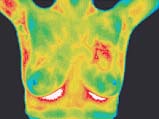

What is Thermography?

Thermography is the Newest, Hottest, technology in preventative care. A Breakthrough in Early Risk Detection of Disease. DITI Scans are 100% Safe, No Radiation, FDA Approved Meditherm Digital Infrared Thermal Imaging is NOW available in Dr. Swerdloff's Santa Monica's office. |

Sample use of Thermography in Breast Cancer

Today, breast cancer is a major health risk to all women because it silently grows and destroys uninterrupted for 10+ years. Thermography can improve the chances for detecting fast-growing, active tumors in the intervals between mammography screenings or for women under 50 years of age. |

Thermography, or Digital Infrared Thermal Imaging (DITI) is a

noninvasive diagnostic technique that allows the examiner to visualise

and quantify changes in skin surface temperature.

A

DITI scan can detect Breast Cancer at VERY EARLY STAGES. This 15 minute

non-invasive Thermogram test from Dr. Lauren Swerdloff, a Board Certified Family Physician practicing

antiaging alternative integrative Family medicine in Santa Monica, is a valuable

procedure for alerting your GP or specialist to the possibility of underlying

breast disease.